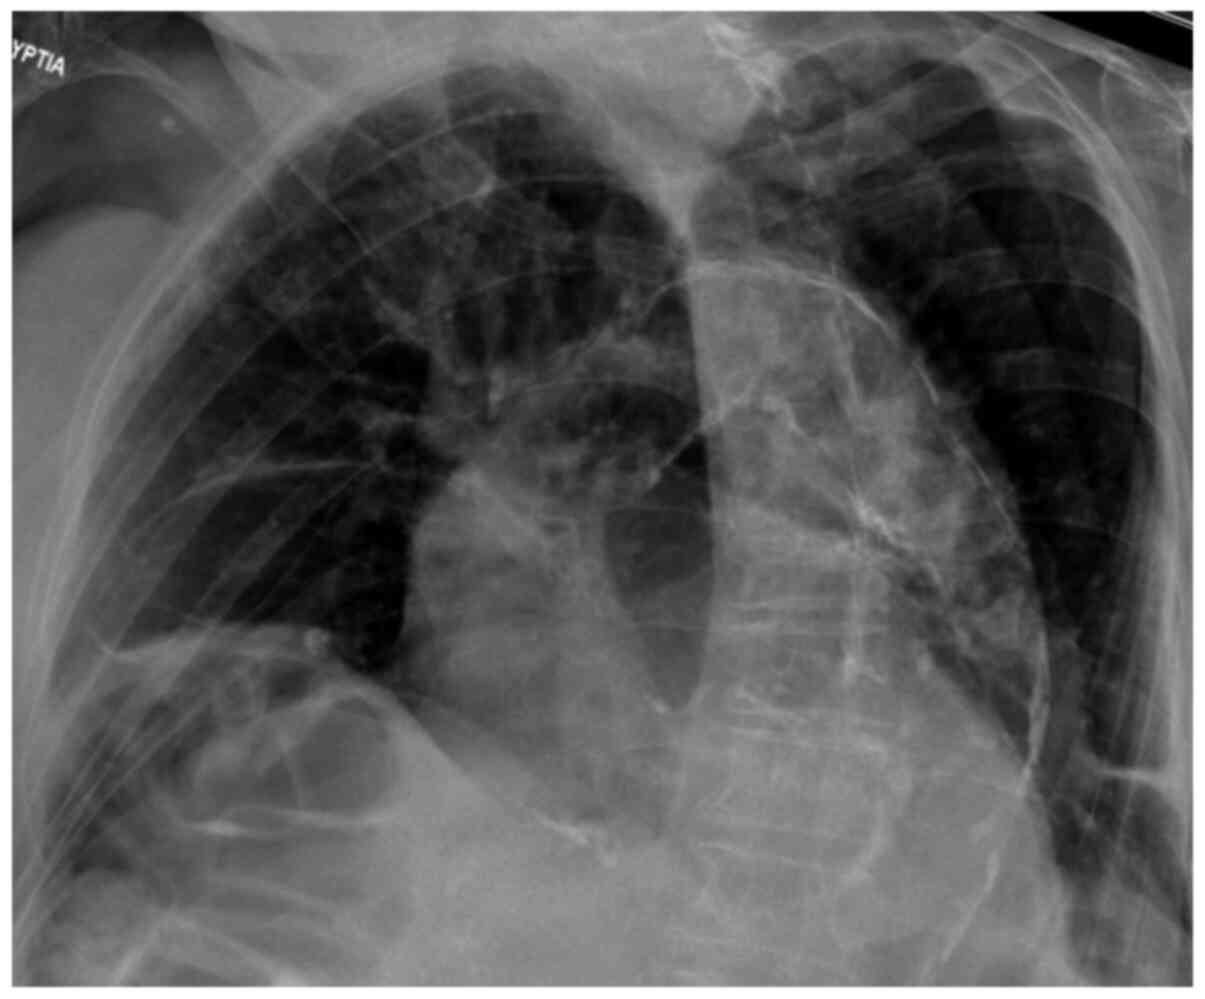

Figure 1